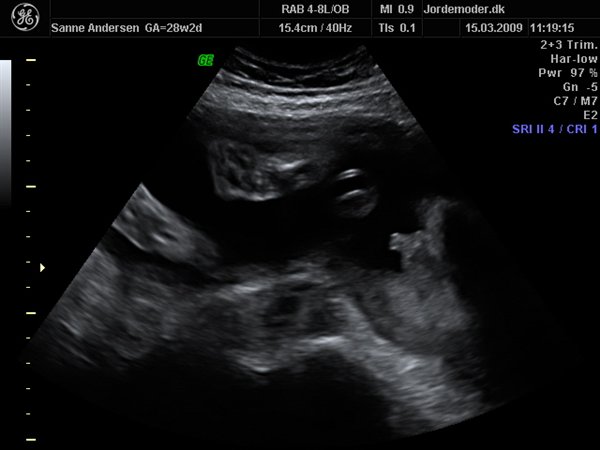

Det gik bare så godt til scanningen, men den ville meget heller sove end være aktiv så vi kunne få en masse forskellige billeder... men vi har fået en masse dejlige billeder og en dvd hvor der er masser af hjertelyd og rigtig pænt billede af hvordan hjertet slår

men vi venter en lille dreng, vi kunne desværre ikke få billede i 3d da han bare ikke ville rykke på sig og han lå så der var for meget fostervand...

Vedhæftede fotos (klik for at se i fuld størrelse)